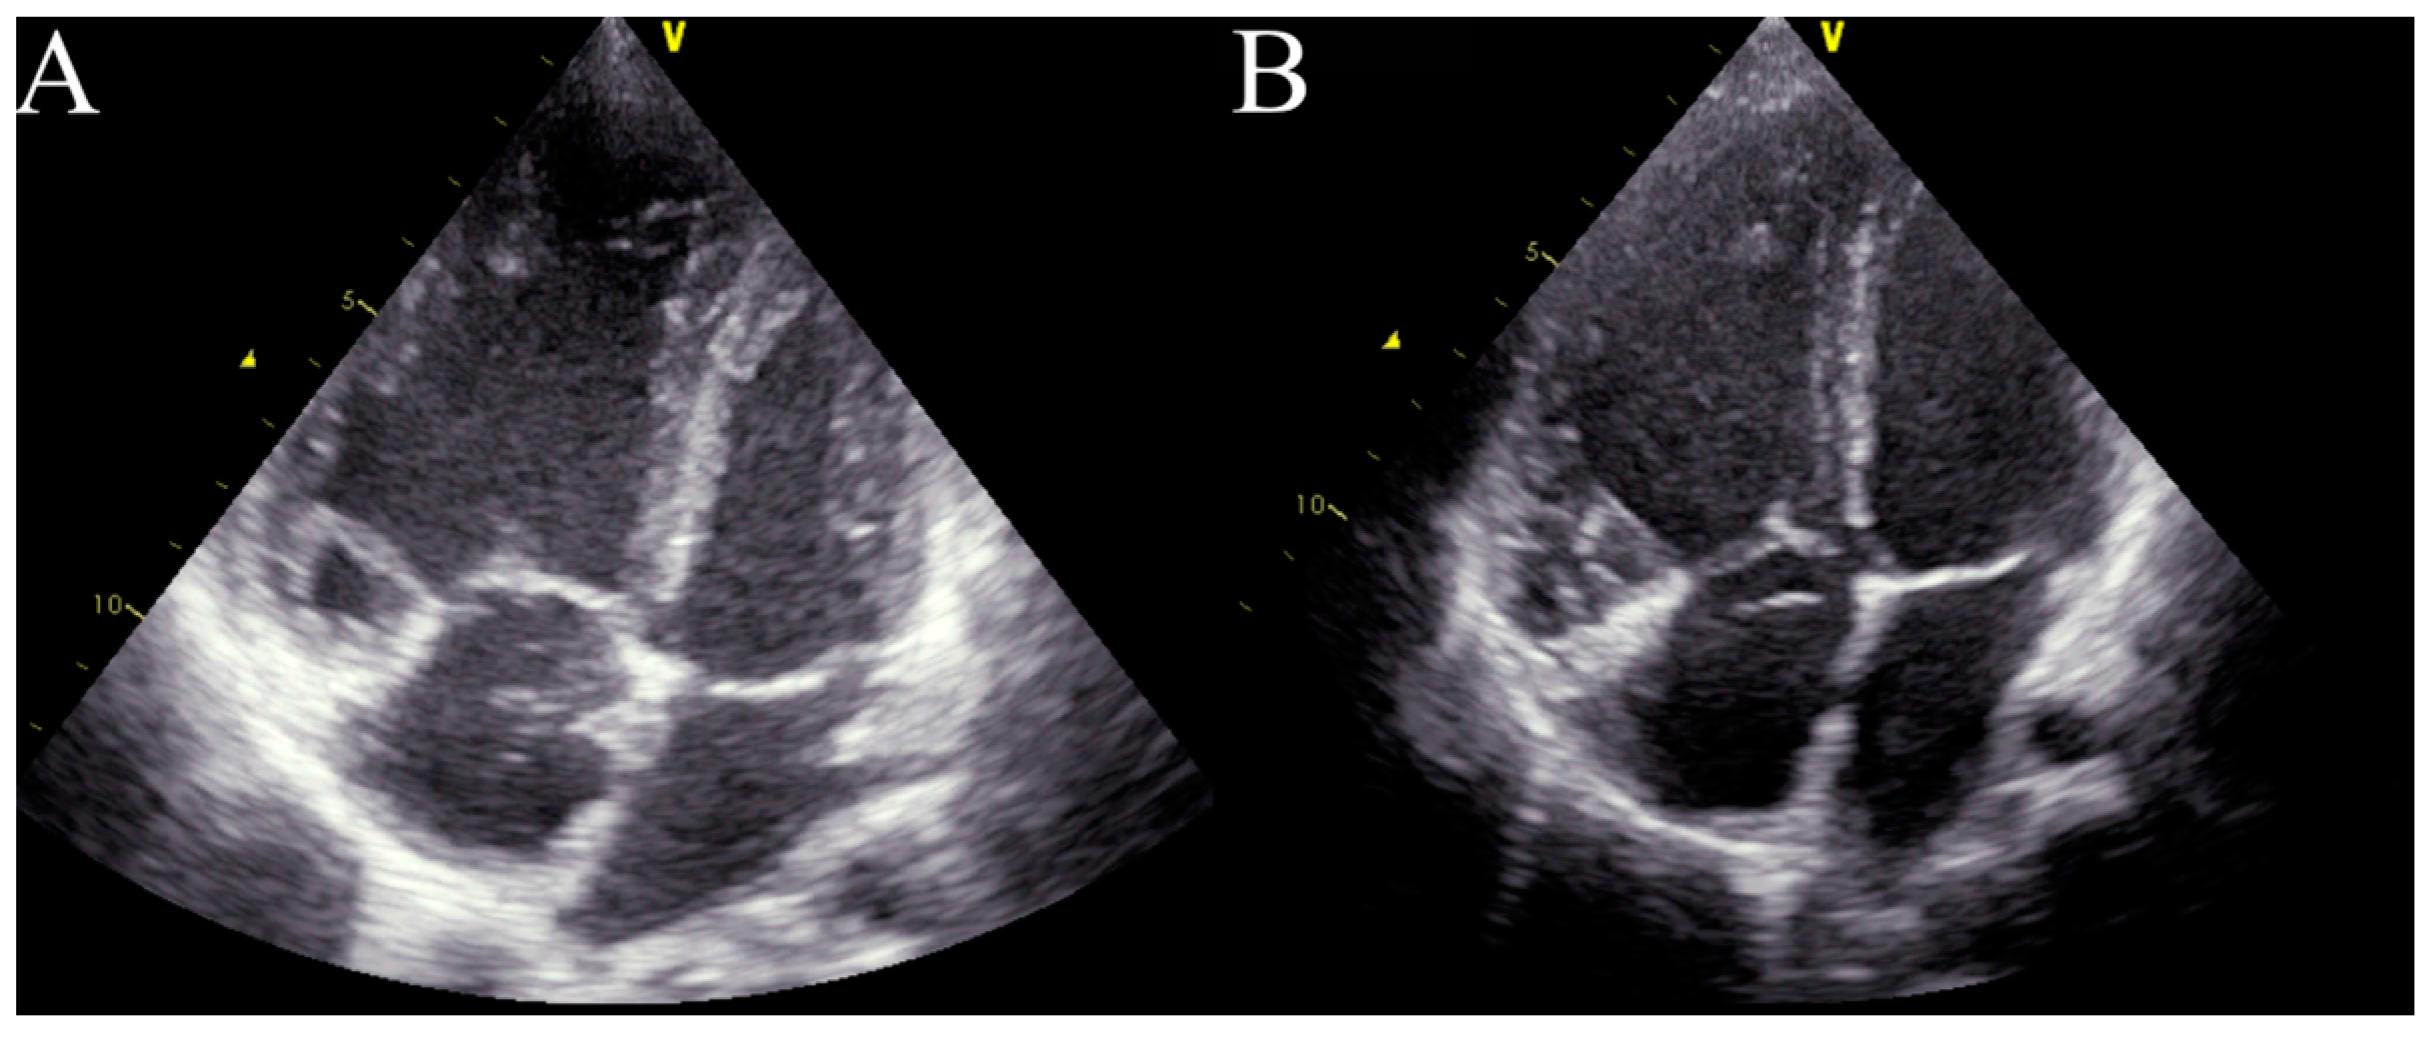

Four months after treatment initiation, the patient’s condition started to deteriorate. Moreover, the patient demonstrated central cyanosis associated with low arterial saturation (78%). A physical examination revealed bilateral, subscapular crackles and dyspnoea on minimal exertion (WHO-FC III/IV). Echocardiography showed the progression of the patient’s RV dysfunction with a further diameter enlargement to 3.3 cm (z-score + 2.36), dilatation of the PA to 3.1 cm (z-score + 4.3), and an increase in the assessed RVSP to 92 mmHg (Figure 2A). The quick progression of the disease after PAH-targeted therapy initiation, with the accompanying signs of pulmonary congestion, impaired gas exchange with a diffusing capacity of the lungs for carbon monoxide (DLCO) at 70%, and a suggestive CT image with centrilobular ground-glass opacities and lymphadenopathy, raised suspicion of pulmonary veno-occlusive disease (PVOD) as the underlying cause of the patient’s pulmonary hypertension [2]. After consultation with an expert transplant centre in Geneva (Hôpitaux universitaires de Genève), the PAH-specific treatment was suspended. The pulmonary vasodilators were withdrawn, and a diuretic treatment with furosemide (10 mg twice daily) and spironolactone (12.5 mg twice daily) was started. However, the patient’s condition continued to deteriorate. In the meantime, the patient had an additional consultation in Vienna (AKH University Hospital) with additional genetic tests, where no pathological mutation was found, and PVOD suspension was doubtful. A decision to reinitiate the PAH-targeted therapy with sildenafil (20 mg thrice daily) and bosentan (31.25 mg twice daily) was made. Finally, the patient was allocated to the waiting list for bilateral LTx (BLTx). Due to her continuing clinical deterioration, the patient qualified for triple therapy with a parenteral prostacyclin analogue. A continuous subcutaneous infusion of treprostinil was initiated and titrated at 2 ng/kg/min every 24 h at the dosage of 17 ng/kg/min. A more aggressive approach in dose escalation is supported by the current adult and paediatric data, but at the time, this option was not available in Poland [3,4,5,6]. However, Haarman et al. found that one year after upfront triple therapy had been started, a substantial number of children with IPAH were considered to need additional intervention, mainly due to their lack of improvement or clinical worsening [6]. After treprostinil administration, the patient’s clinical status improved (WHO-FC II, 6MWT distance 510 m), and this led to stabilization during the time spent waiting for BLTx, albeit without significant haemodynamic improvement. Only the RV diameter was found to be decreased in the echocardiographic assessment, with a drop to 2.7 cm (z-score + 1.44) 3 months after treprostinil administration (Figure 2B).

Figure 2. Echocardiography in critical care. (A)—right ventricle enlargement in the apical four-chamber view before treprostinil administration. (B)—right ventricle enlargement in the apical four-chamber view 3 months after treprostinil administration.